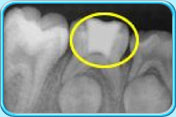

图中所见是一张X光片,显示一颗接受了清除部分牙髓的治疗之后的乳臼齿。治疗后